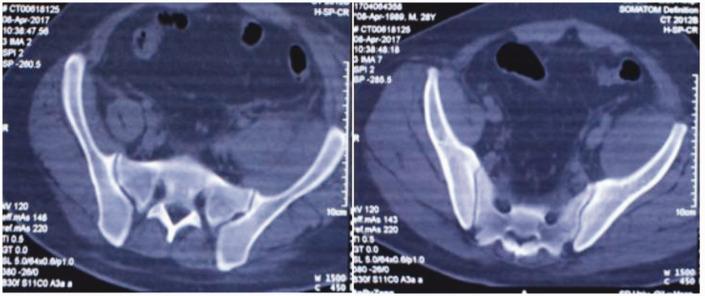

Acquired haemophilia A (AHA) is a rare haemorrhagic disease characterized by spontaneous extensive subcutaneous haemorrhage and soft tissue haematoma. The activated partial thromboplastin time is significantly prolonged and cannot be corrected by normal plasma. Approximately 50% of AHA patients lack a specific aetiology, so this can easily result in a misdiagnosis. This current case report describes a 27-year-old male that presented with gingival bleeding, haematuria and haematochezia with no obvious cause. At first, it was thought that he might have experienced anticoagulant rodenticide poisoning, but the subsequent anticoagulant rodenticide test was negative. At the same time, the patient was screened for mutations associated with bleeding and coagulation diseases. Two mutations were identified: a p.Y471H mutation the plasminogen activator, tissue type () gene; and a p.Y244Y mutation the serpin family E member 1 () gene. It should be noted that patient had no previous history of thrombosis or haemorrhagic disease, which confused the diagnosis. A professional haemophilia research centre provided clarification of the diagnosis when anti-factor VIII antibodies were detected. The patient was treated with 30 mg/day prednisone orally. Multiple follow-up examinations showed continuous complete remission. No factor VIII antibodies were detected in his blood and coagulation factor VIII increased significantly.

获得性血友病 A (AHA) 是一种罕见的出血性疾病,其特征为自发性广泛皮下出血和软组织血肿。活化部分凝血活酶时间显著延长,且不能被正常血浆纠正。约 50%的 AHA 患者缺乏特定病因,因此容易导致误诊。本病例报告描述了一名 27 岁男性,因牙龈出血、血尿和血便就诊,无明显病因。起初,考虑可能是抗凝剂中毒,但随后的抗凝剂检测为阴性。同时,对患者进行了与出血和凝血疾病相关的基因突变筛查。发现了两个突变:纤溶酶原激活物,组织型(p.Y471H)基因和丝氨酸蛋白酶抑制剂家族 E 成员 1(p.Y244Y)基因。值得注意的是,患者无既往血栓或出血性疾病史,这增加了诊断的难度。当检测到抗因子 VIII 抗体时,专业的血友病研究中心明确了诊断。给予患者 30mg/天泼尼松口服治疗。多次随访检查显示持续完全缓解。患者血液中未检测到因子 VIII 抗体,凝血因子 VIII 显著增加。